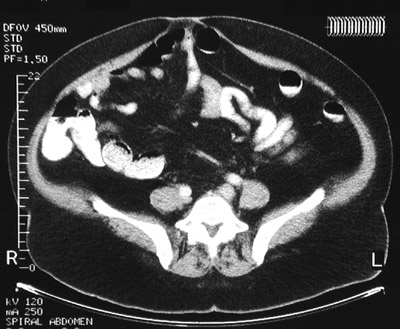

| Here is an umbilical hernia as seen in an abdominal CT scan. Note the loops of bowel extending close to the skin surface in the hernia. A hernia occurs at a weak point in the abdominal wall. Inguinal hernias are more common, but the umbilical region can also be involved. |